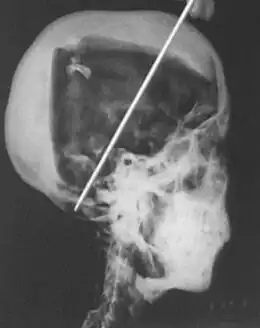

Radiografías realizadas en 1968

En 1968, R.G. Harrison, profesor de anatomía, utilizó una máquina de rayos X portátil para tener una mejor visión de la conformación interna de la momia y así determinar mejor la edad y la causa de la muerte de Tutankamón. Uno de los hallazgos más anormales fue que el esternón —hueso del pecho— y la mayor parte de las costillas frontales faltaban. La eliminación de estos huesos no era parte del proceso de momificación normal, lo que llevó Harrison a creer que podrían haber sido eliminados porque estaban muy dañados antes de su muerte. Harrison descubrió rápidamente que Carter no fue tan cuidadoso como dijo en muchas de sus notas personales. La momia no fue reenvuelta después de 1926, lo que llevó a un mayor deterioro debido a los elementos externos extremadamente calientes durante cuarenta y dos años. También parte de la piel y el esqueleto fue dañado con el fin de extraer la joyería. Ambas manos estaban cortadas, las dos piernas fueron retiradas de la pelvis, y la cabeza fue separada del cuerpo con el fin de obtener la máscara. Aún más notable es que la oreja derecha del rey y el pene faltaban, pero las fotografías de Carter muestran que ambos estaban presentes durante el examen. Harrison cree que la curva leve en la columna vertebral y los pequeños fragmentos de hueso podría haber sido el resultado del proceso de embalsamamiento. La lesión en la mandíbula izquierda mostró signos de curación que ocurrieron antes de su muerte, también una de sus piernas se había roto, pero no se pudo determinar si ocurrió de forma natural o como resultado del embalsamamiento o el examen de Carter. El hecho de que se descubrieron fragmentos de cráneo llevó a muchos a suponer que el rey fue asesinado por un golpe en la cabeza, pero la radiografía no podía apoyar o desacreditar esa teoría.[10]